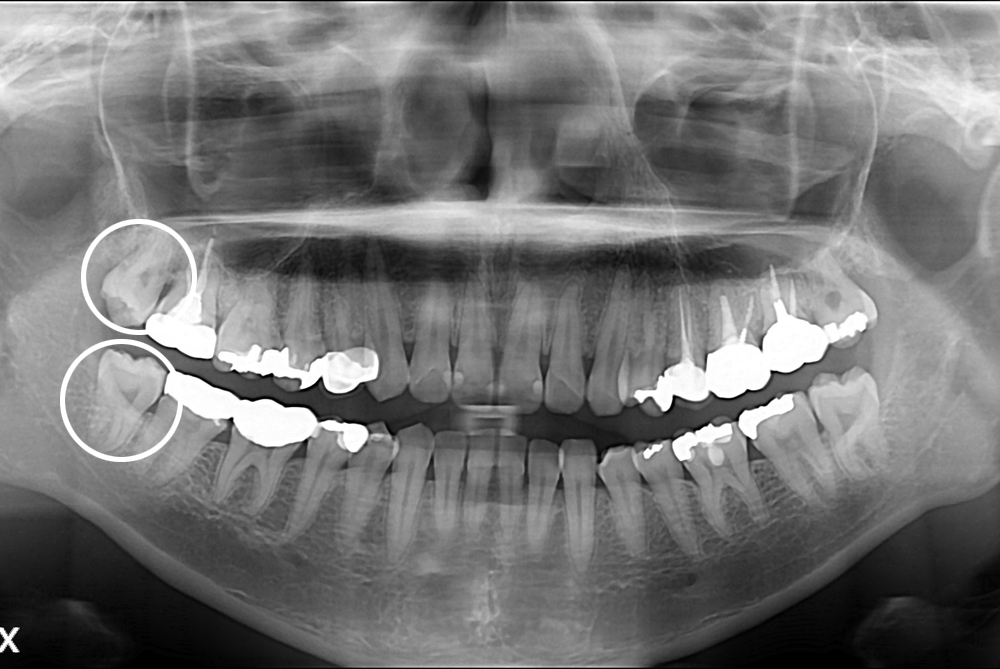

치료사례

세종치과의 진심 어린 치료는 결과로 말합니다.

실제 내원하신 환자분들의 치료 전·후 사례를 확인해보세요.

모든 치료사례 전후사진은 환자분의 동의하에 촬영되었습니다.

모든사진은 동일 환자분의 전후모습을 촬영하였으며, 사진의 밝기조절 외에 임의 수정이 없음을 알려드립니다.